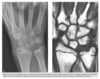

A 21-year-old man with worsening pain in the left wrist after an injury 6 months earlier (Fig. 2.13.1).

Figures 2.13.2 and 2.13.3 are of a 46-year-old man with wrist pain

Anteroposterior view of the left wrist

(Fig. 2.13.1) shows an ulna that is shorter than the

radius (i.e., negative ulnar variance or ulnar minus

variance) and a lunate that is sclerotic and some-

what irregular in shape.

Kienböck disease (i.e., lunatomalacia)

Kienböck disease, or lunatomalacia, is

osteonecrosis of the lunate. It is most common in

­ patients 20 to 40 years old and has a predilection

for the dominant hand in individuals involved

in manual labor.

Cause unknown

shortened ulna

in relation to the radius (i.e., negative ulnar variance

or ulnar minus variance) is seen in up to 75% of pa-

tients with lunatomalacia and is considered a major

cause of the disorder

The imaging findings, which do not always corre-

late with the patient’s symptoms, include increased

density or sclerosis of the lunate and, eventually, alteration in the normal bony shape with collapse

on radiographs.

For example, in a 46-year-old

man with wrist pain, a coronal T1-weighted image

(Fig. 2.13.2) demonstrates low signal intensity in

the lunate (arrow) and negative ulnar variance. The

gradient-recalled echo MR image (Fig. 2.13.3) shows

the signal intensity within the lunate to remain low

(arrow). These features are diagnostic of osteone-

crosis (i.e., Kienböck disease). Surgical intervention

includes lunate replacement, radial shortening, and

ulnar lengthening.